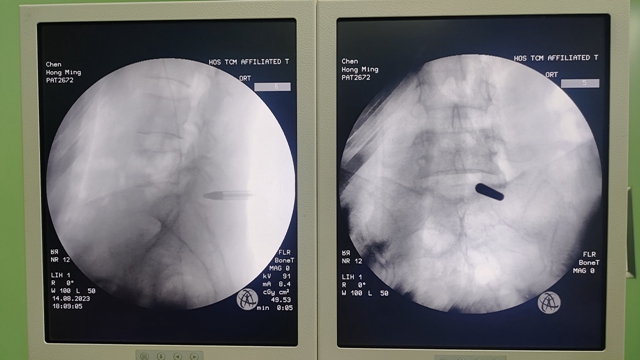

骨伤科脊柱·肿瘤一组团队经过讨论,为陈嬢嬢拟定了微创手术治疗方案——内镜下L5-S1椎管扩大减压+椎间盘髓核摘除术,在征得陈嬢嬢及其家属同意后,谢明忠副教授和古钦文主治医生顺利实施了手术。

术中采用俯卧位,在陈嬢嬢背部开了一个约7mm的手术切口,术中清晰分辨椎管内神经根及硬膜囊等神经组织,顺利摘除“突出的椎间盘组织”,手术过程十分顺利。术后陈嬢嬢疼痛症状明显缓解,第二天就可以下床独立行走。